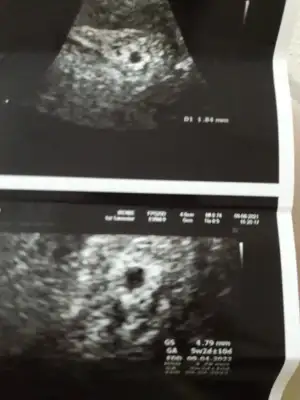

Amin canım dualarım hepimiz için benim ultrasona bakarmisin 5+2 mi anlamadım yolk keseside 1.84mm . 2.5 in altı sağlıksız gebelik sayılıyormus öyle okudum bi yerde😔

5 hafta 2 günlük kuzum kese 4cm yolk 1.84 mm oda 5 haftalık gebelik için gayet normal